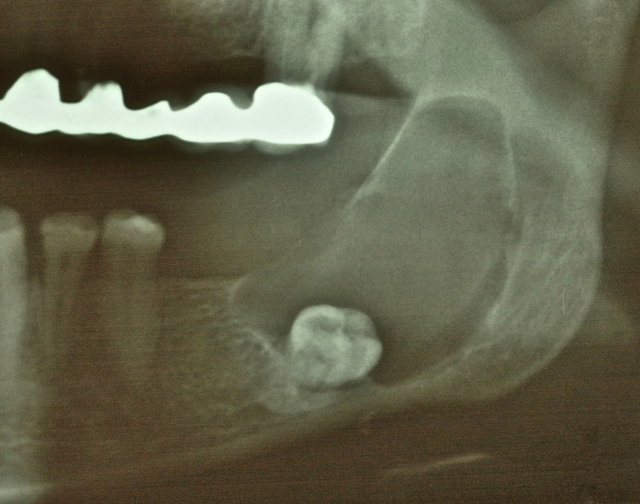

Orthopantomographie (OPT)

Verlagerung der Weisheitszähne

Follikuläre Zysten um die unteren beiden Weisheitszähne